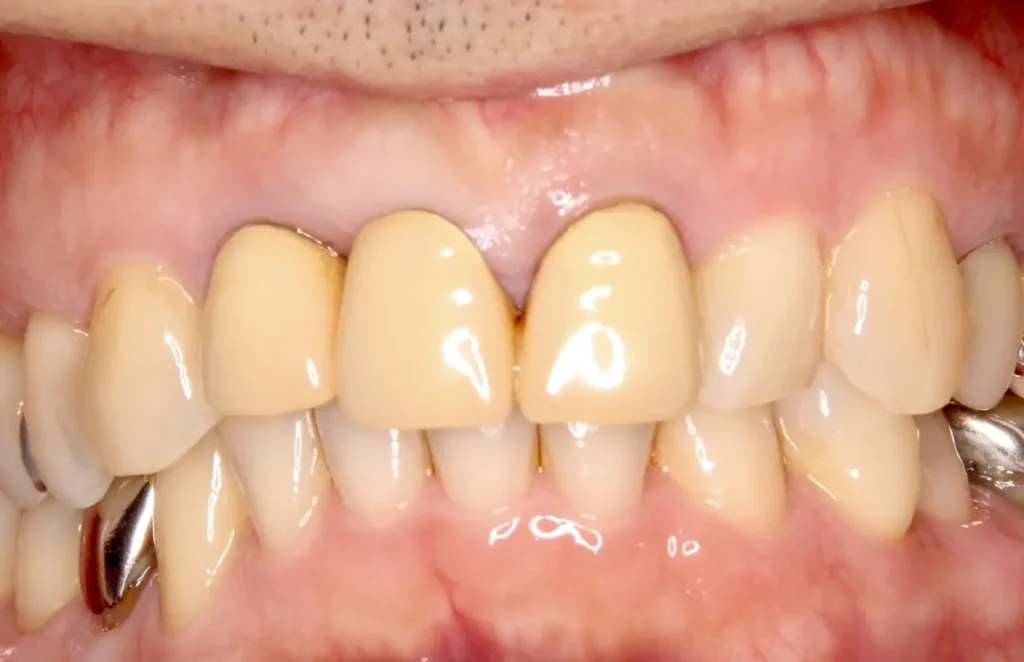

口腔内写真

術後3年レントゲン写真

根の周りが白っぽく骨ができています

術後1年口腔内写真

外科的処置の跡はほとんどなく、ブリッジも自然な感じで歯がないようには見えません